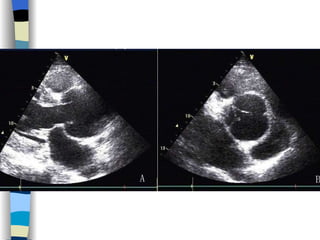

Echocardiography The most valuable technique for diagnosing MS, and determining its severity M-mode echo : Thickened, calcified leaflets open poorly, close slowly (EF slope ↓ ) The double peaks disappear Both leaflets move anteriorly during early diastole Two-dimensional echo: Fusion, thickening,  doming  of the valve leaflets, and poor leaflet separation in diastole;  mitral orifice area ↓

Doppler echo : Most accurate noninvasive technique for quantifying the severity of MS Spectrum Doppler: measure transvalvular gradient, MVA Color Doppler: display  high velocity color jet Provide other important information Cardiac chamber size (LA, RV) Left ventricular contractility Pulmonary arterial pressure Other coexisted valvular or congenital abnormalities  Mural thrombi

Echocardiography 1 、 Display anatomy of the mitral valve apparatus Useful in determining the etiology of MR ( 2D ) 2 、 Confirm the existence of MR Doppler   (color, spectrum): reveal high-velocity jet into LA during systole Sensitivity~100% Estimate the severity of MR < 4 cm2  Mild ( Color flow jet area )  4~8 cm2  Moderate  > 8 cm2  Severe 3 、 Measure cardiac chamber sizes, evaluate LV function, pulmonary artery pressure, provide data concerning other valvular lesions

Echocardiography Establish a diagnosis, and determine the severity of AS M-mode and 2D echo  Observe aortic valve opening, thickening and calcification Helpful in determining the etiology of AS Also invaluable in detecting associated mitral valve disease and in assessing LV performance, hypertrophy, and dilatation

Doppler  echo Allows calculation of the aortic valve gradient Estimate the severity of the stenosis <  30 mmHg  Mild AS MPG  30~50 mmHg  Moderate AS > 50 mmHg  Severe AS  Color Doppler flow imaging is helpful in the detection and determination of the severity of any accompanying aortic regurgitation

Echocardiography   Confirm diagnosis, estimate severity, identify the cause 2-D echo:  Structural changes  of the valve leaflets and/or aortic root M mode echo:  Diastolic fluttering  of the anterior leaflet of the mitral valve is an important echocardiographic finding in AR Serial assessments of LV size and function Doppler echo:  Sensitive, accurate noninvasive technique for detecting AR LVOT diastolic  regurgitant  jet , estimate the severity of AR Cardiac catheterization Quantify the severity of AR Evaluate the coronary and aortic root anatomy